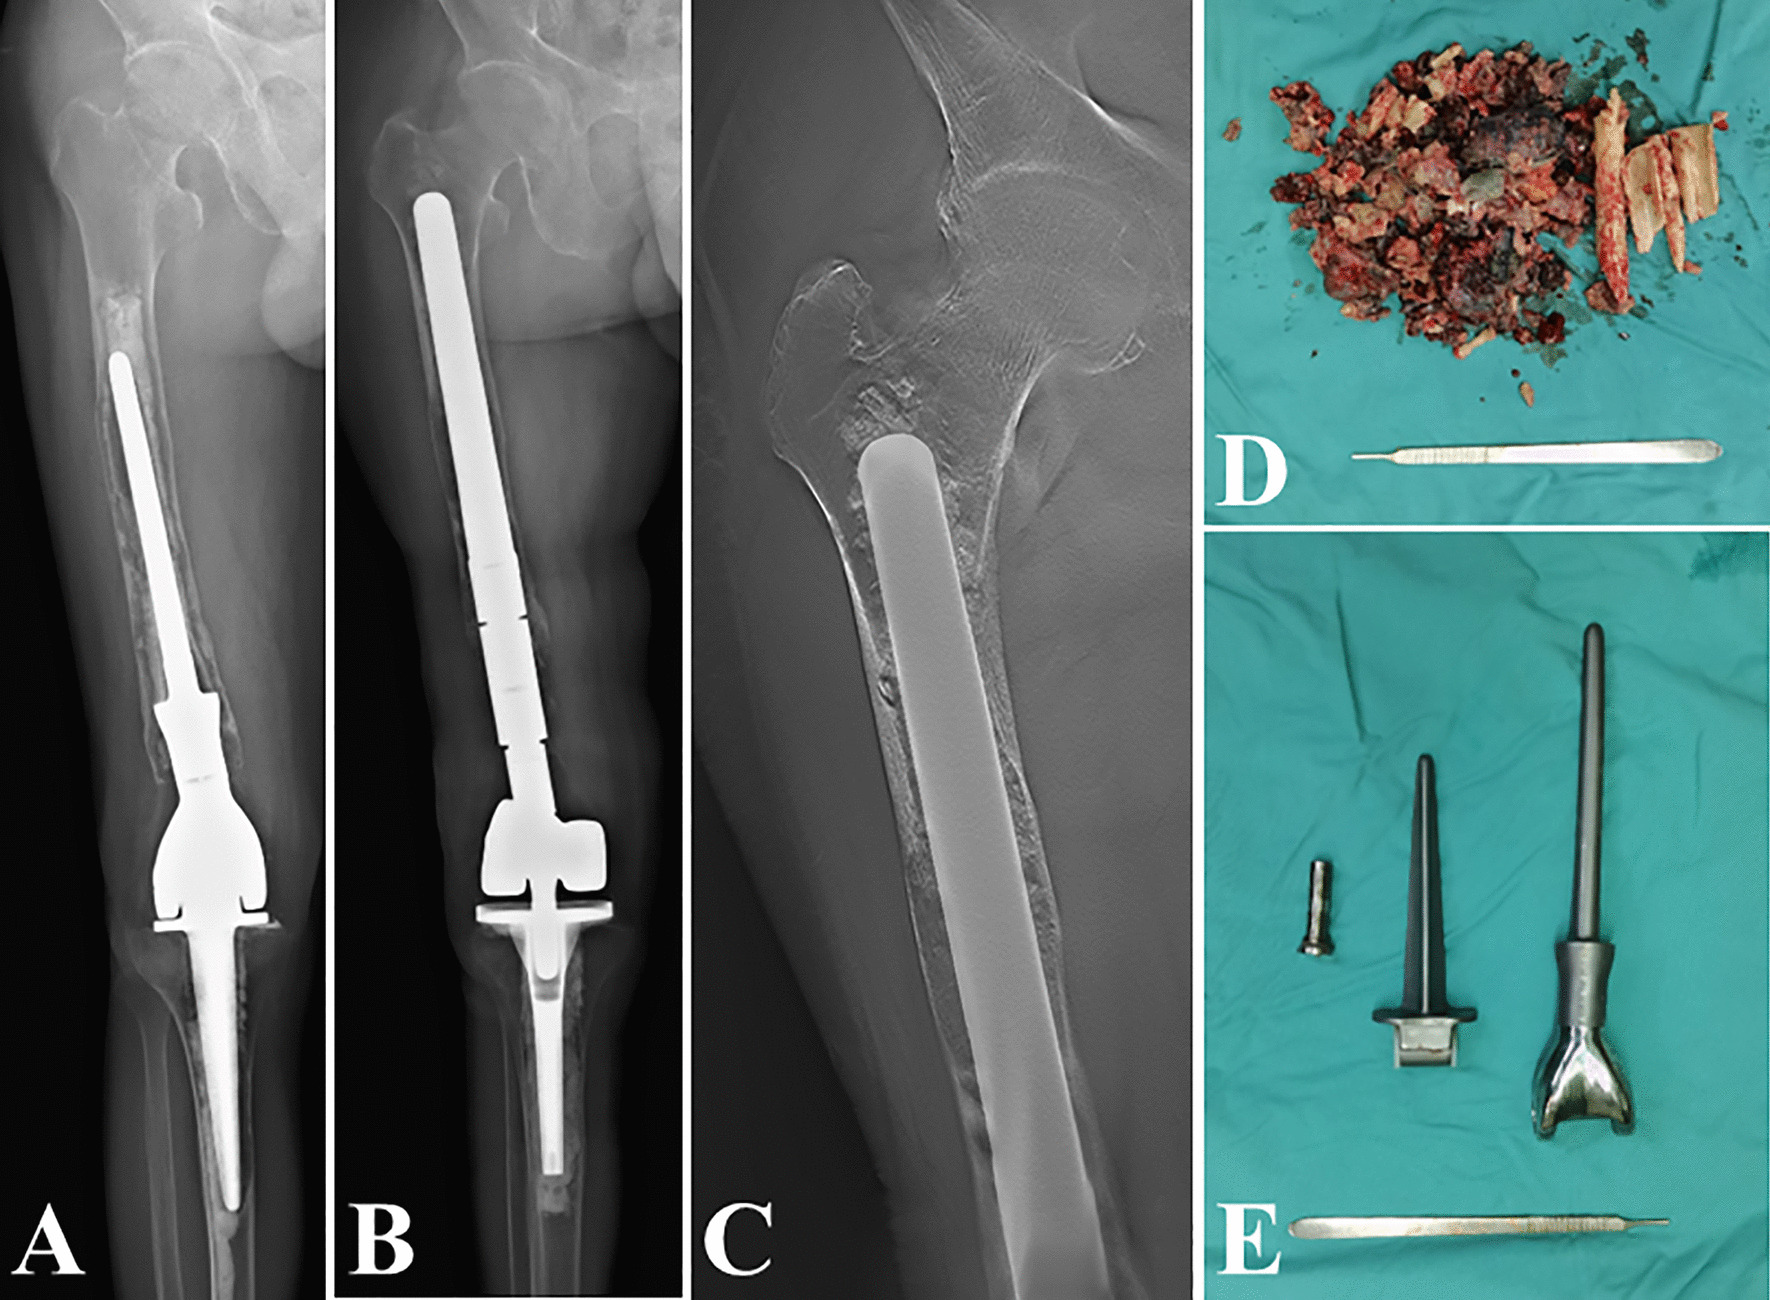

Radiologic results

The postoperative immediate radiographic showed that the revision stem matched the femoral anterior curvature well. The femoral bone defect was completely filled by the 3D design stem in 10 of the 17 cases. In the remaining cases, persistent peri-stem defect was observed. The majority of the defects were located in the proximal femur (Fig. 7). At the last follow-up examination, defects were no longer radiologically visible in 4 of the 7 femurs. Partial restoration of defects could be observed in the remaining 3 femurs. The area of osteolysis was also markedly reduced. Re-aseptic loosening did not occur, and postoperative development of new femoral bone loss was not observed.

Fig. 7.

Radiographs demonstrating that the peri-stem remaining defect can be filled or partially restored during the follow-up. The bone defect was filled in the proximal femoral (A, B), distal femur (C, D), and both proximal and distal femur (E, F). The bone defect partially restored (G, H)